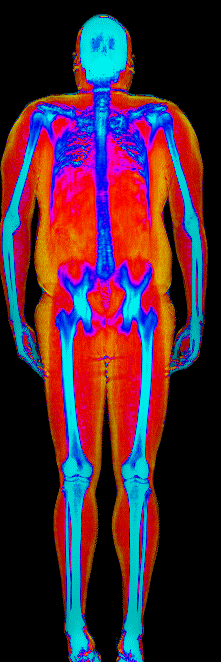

What Muscle Gain Looks Like on a DEXA Scan

Gained 12.0 lb lean, lost 24.9 lb fat · 183 → 170 lb · Age 37

Gained 10.0 lb lean · 140 → 152 lb · Age 23